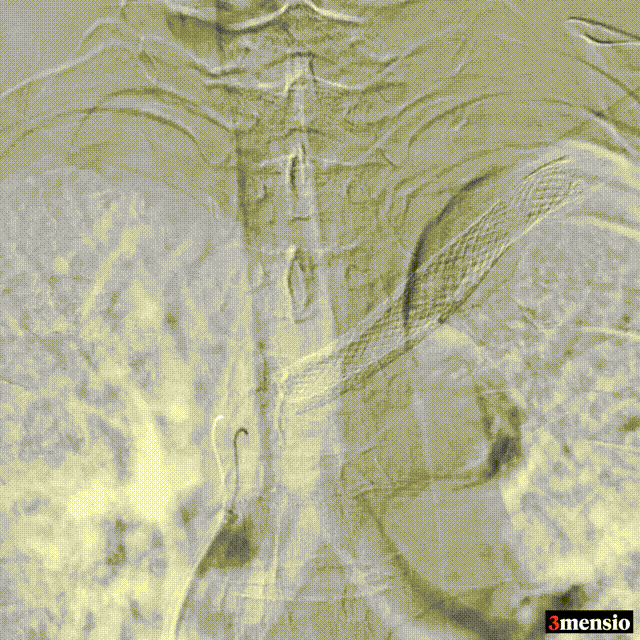

�� 病例四:左头臂干静脉狭窄、闭塞

图:手术过程

�� 病例五:左侧头臂静脉狭窄